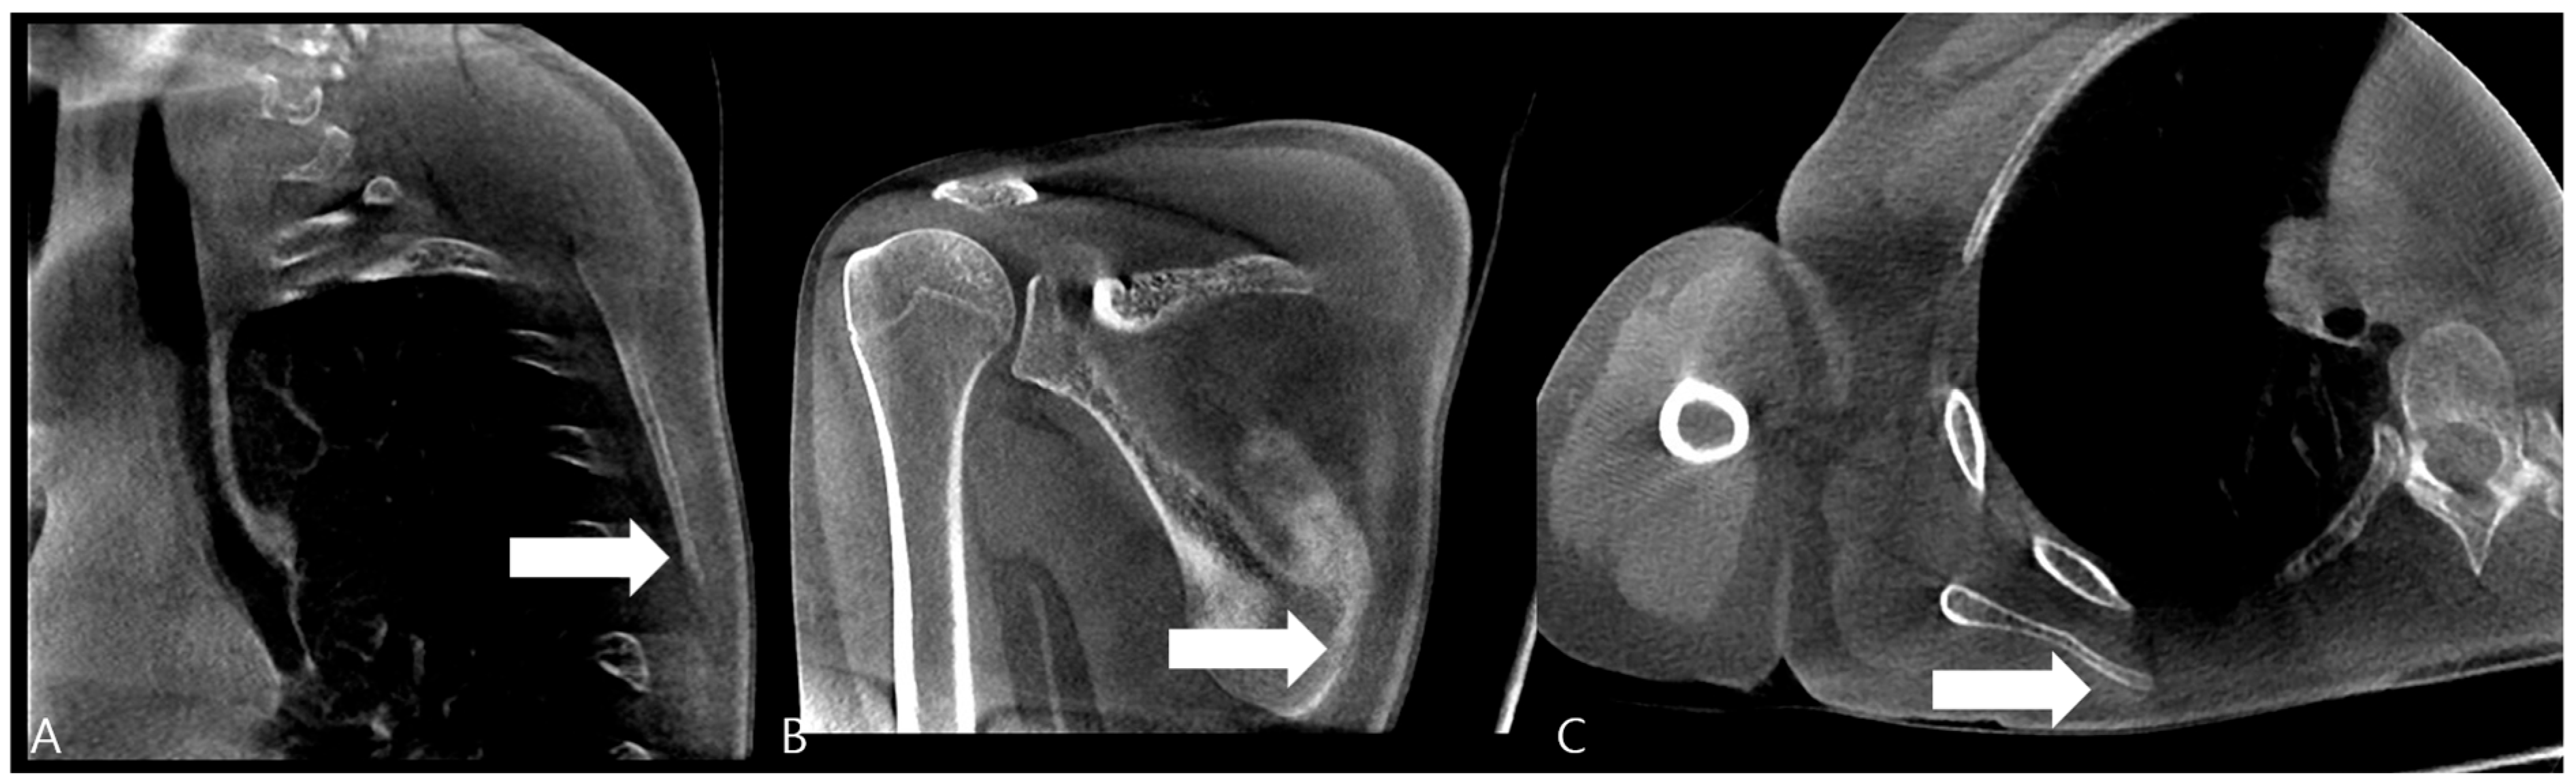

Over a two-month follow-up period, the patient showed a gradual increase in punching power, and discomfort in the scapular region improved. At the three-month follow-up, a computed tomography (CT) scan of the right scapula was obtained to confirm the sonographic diagnosis. The CT images clearly revealed a cortical break with associated periosteal reaction at the medial border of the scapular body, corresponding precisely to the site of sonographic irregularity and point tenderness, thus definitively confirming the diagnosis of a stress fracture (Figure 3).

Figure 3. Computed Tomography (CT) of the Right Scapula. (A) Cortical breakage and callus formation are observed on the medial side of the scapular in the sagittal image (white arrow). (B) Callus formation (white arrow) and periosteal reaction are observed on the inferior part of the scapular medial border in the coronal image. (C) Callus formation is observed on the scapula medial border in the axial image (white arrow).